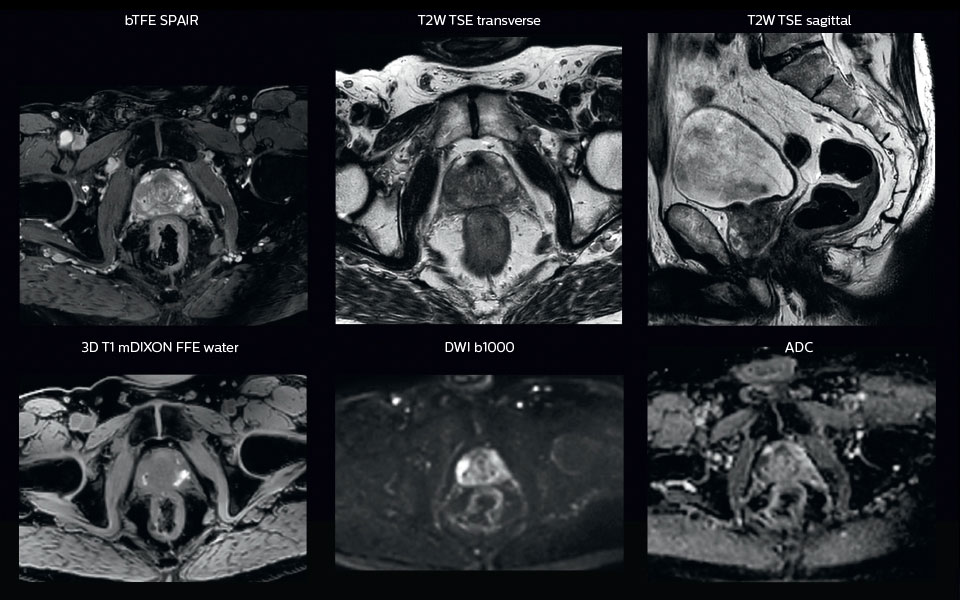

“When we can visualize intraprostatic lesions, the radiation therapist can then plan to boost them, giving a higher dose to those lesions instead of giving a uniform dose to the whole prostate, in the hope to better treat the patient and have less risk of recurrent tumors. However, this is not yet clinical routine. For visualizing the lesions, we not only use anatomical, T2-weighted imaging, but also diffusion weighted MRI and dynamic contrast- enhanced MRI."

A 63-year-old patient with prostate cancer, cT3bNxM, Gleason 7, underwent MRI on Ingenia 3.0T MR-RT before radiation therapy.

Intraprostatic lesions are visible on the bTFE MR image, but not on the CT image. MRI shows excellent soft-tissue contrast for the visualization of critical structures like the rectum and penile bulb.